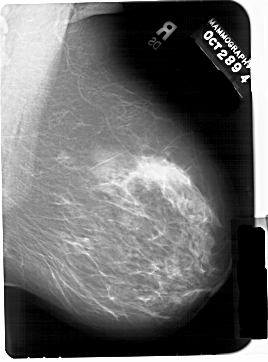

A_1438_1.RIGHT_MLO

RIGHT_MLO LINES 6871 PIXELS_PER_LINE 5086 BITS_PER_PIXEL 12 RESOLUTION 43.5 NON_OVERLAY